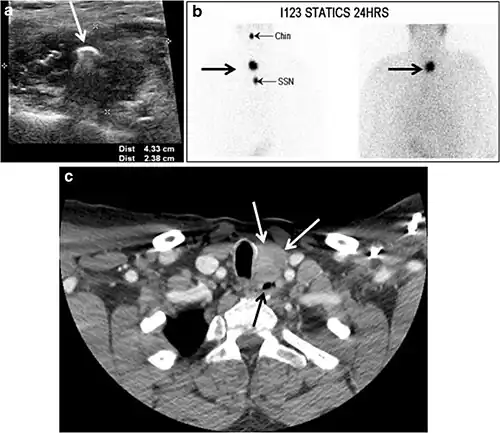

Fig. 8. A 48-year-old male patient post total thyroidectomy with PTC recurrence. a Transverse greyscale ultrasound of the neck demonstrates a left thyroid bed heterogeneous, predominantly hypoechoic irregular lesion with calcifications (white arrow). b A spot image of iodine 123 total body scan of the neck demonstrate a focus of abnormal radiotracer uptake at the left thyroid bed (Black arrows) between the annotated markers. c Enhanced axial CT scan of the neck demonstrates an enhancing large left thyroid bed mass (white arrow) with no calcifications. The lesion exerts a mass effect on the oesophagus (black arrow) and is inseparable from the trachea.[1] -